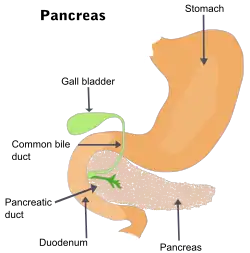

The prognosis still remains poor. The cancer commonly spreads to the liver, bile duct, stomach, and duodenum.[24]